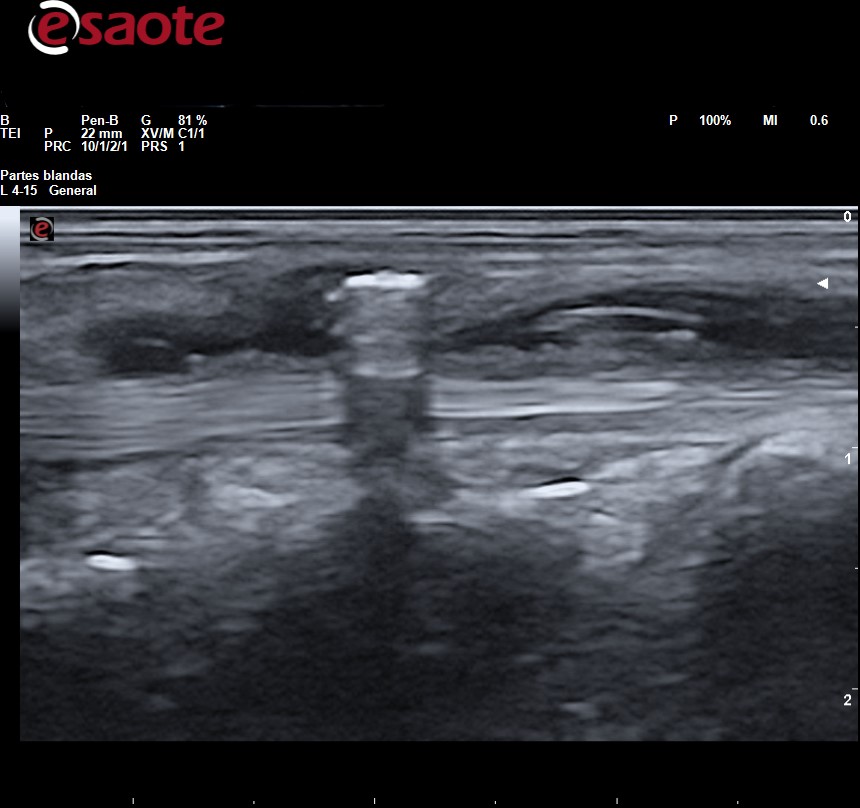

Observamos en el tejido celular subcutáneo imagen lineal hiperecogénica con artefacto de reverberación

La Rx es la primera técnica de diagnóstico para identificar y localizar cuerpos extraños, sin embargo, en ella solo pueden apreciarse la presencia de fragmentos radiopacos (metal, vidrio, piedra y algunos plásticos). Los fragmentos de madera, espinas de plantas y de pescados son indetectables. La Rx da una idea de la ubicación del fragmento y de sus relaciones con huesos y articulaciones adyacentes, pero no puede determinarse la ubicación del fragmento con relación a las estructuras adyacentes: tendones, vasos sanguíneos y nervios que sí podremos determinar con precisión mediante la ecografía lo cual facilita la planificación para su extirpación. Tanto los fragmentos radiopacos como los radiotransparentes se aprecian en ecografía como imagen hiperecogénica con artefacto de sombra acústica posterior o de reverberación según las características del cuerpo extraño rodeada de halo hipo-anecoico si hay granuloma.